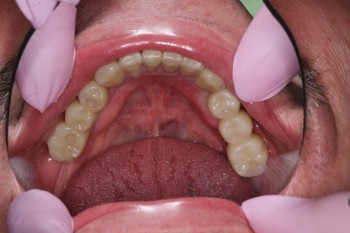

Ястребов Даниил Александрович: портфолио (1)